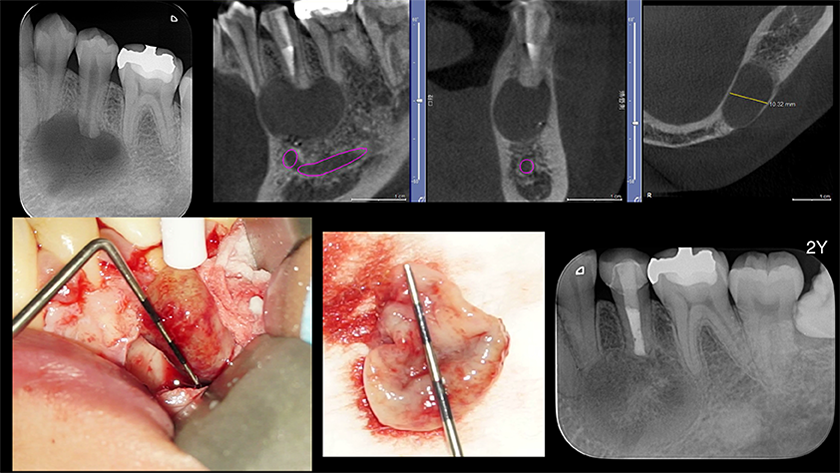

外科的歯内療法

LIVE配信 2026年7月15日(水) 19:30~21:00

見逃し配信:2026年7月29日(水)~8月7日(金)

講演のポイント

・どのような症例で歯根端切除術を選択するのか

・安全に歯根端切除術を始めるために準備する事

・歯根端切除術の適応と非適応

・歯根端切除術の術式をstep-by-stepで!